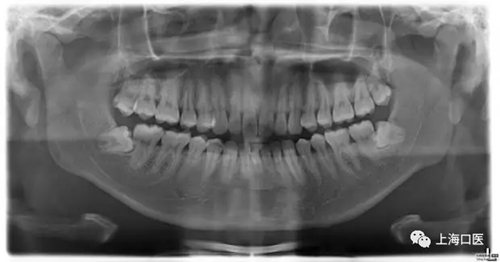

全景片

拔牙干槽癥可怕嗎?